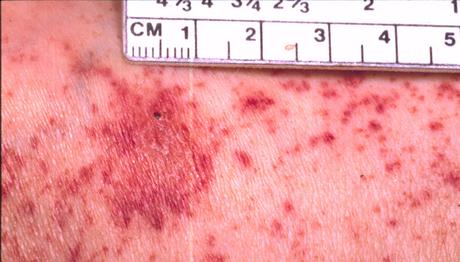

Las manchas de sangre en la piel presentan un diagnostico muy claro, porque como lo hemos venido mencionando, es que se manifiestan en pequeñas manchas rojas y no presentan ninguna molestia física, ni dolor ni picazón. A diferencia de otras erupciones que existen, estas son de apariencia plana y con carencia de relieve. Así que para su diagnostico se debe hacer una vipro-presión, en otras palabras, presionar sobre para ver si desaparecen. Si el resultado es negativo, quiere decir que los glóbulos rojos han salido de los vasos sanguíneos y que se esta en una clara presencia de petequias.

A la hora de identificar la petequias, es el cambio de color que va teniendo con el paso del tiempo y en la mayoría de los casos aparecen en las piernas pero pueden aparecen en cualquier parte. En esta zona, su aparición tiene que ver principalmente al esfuerzo como el vomito, el llanto o la tos y se concentran mas que todo en el contorno del ojo. Se debe tomar en cuenta que la fase inicial de las petequias es que aparecen de manera individual y poco a poco se van agrupando, extendiendo y expandiendo a lo largo del tiempo y de la parte afectada.